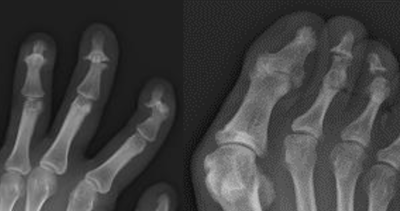

ヘバーデン結節に似た病気 乾癬による手指の関節炎倉石整形外科クリニック 長野市若穂 リハビリテーション科。

乾癬性関節炎かんせんせいかんせつえん 頭皮や全身に赤い発疹を伴う、関節の痛み - 古東整形外科・リウマチ科。